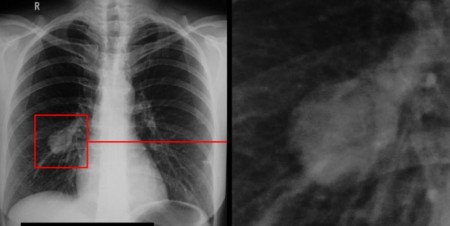

Красноярские медики запатентовали новый метод диагностики рака лёгких

Специалисты Центра ядерной медицины Федерального Сибирского научно-клинического центра ФМБА России разработали и запатентовали инновационный способ диагностики рака лёгких. Новый метод позволит выявлять заболевание на ранних стадиях и обнаруживать даже мельчайшие метастазы.